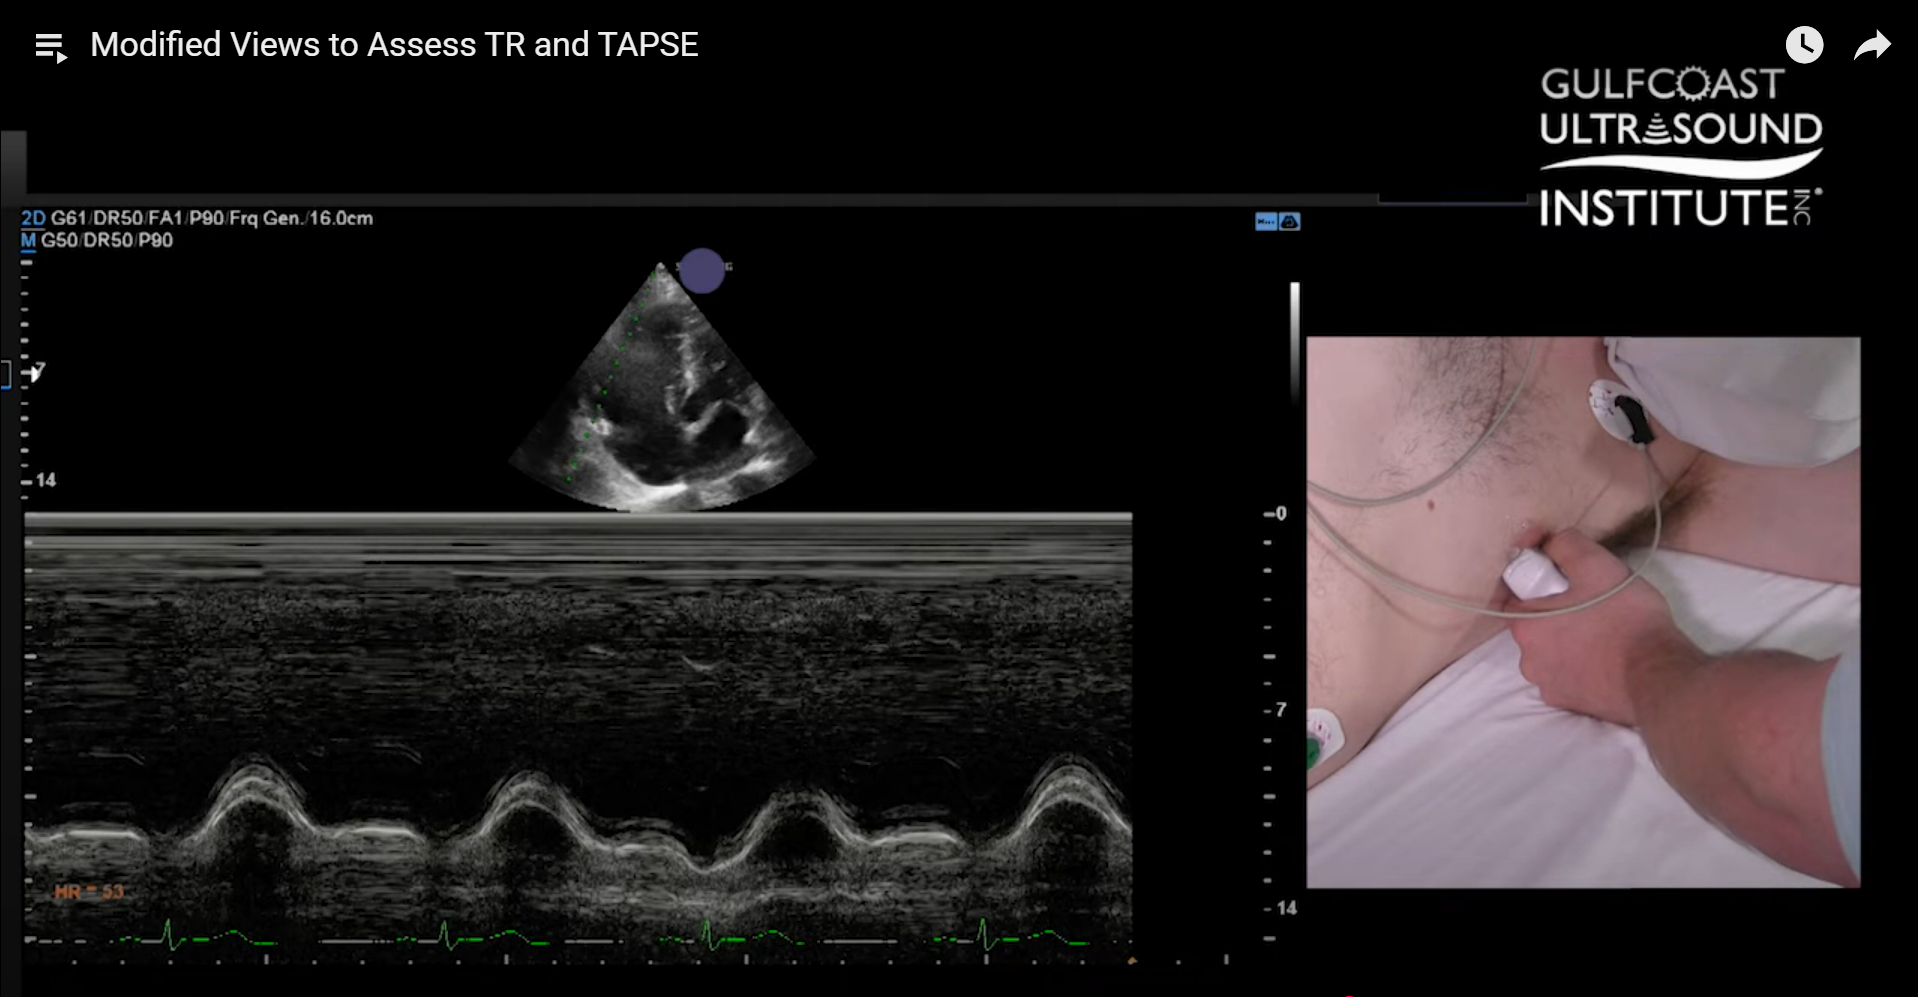

- TAPSE, or Tricuspid Annular Plane Systolic Excursion, is a standard measurement of RV systolic function.

- From the modified apical 4 chamber view, use M-mode at the tricuspid annulus.

- This alignment places the M-mode cursor more directly with the motion of the RV free wall annulus.

- In a standard 4 chamber view, the RV free wall may obstruct alignment.

- The ASE recommends using this modified approach to achieve a crisp, accurate TAPSE measurement.